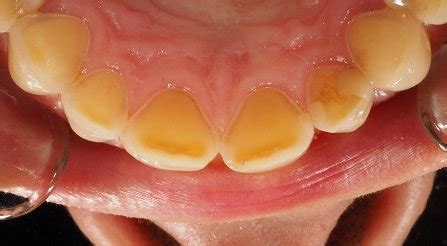

- Decoloración: Cambio de color de los dientes: Con la erosión dental se va perdiendo el blanco inicial de nuestra dentadura. Los dientes pueden parecer amarillentos, ya que la dentina (la capa que se encuentra debajo del esmalte) queda más expuesta.

- Cambios en la forma de los dientes: Dientes que se ven más pequeños, achatados o con superficies planas que antes no tenías. Los huecos en los dientes y el desgaste general de la superficie de los dientes y los bordes de mordida son signos comunes de erosión.

- Transparencia: Transparencia: los incisivos pueden parecer transparentes cerca de los bordes con los que muerdes.

- Grietas y hendiduras: Grietas y hendiduras: si el esmalte dental empieza a erosionarse, los dientes pueden presentar pequeñas grietas y hendiduras en la superficie masticatoria.